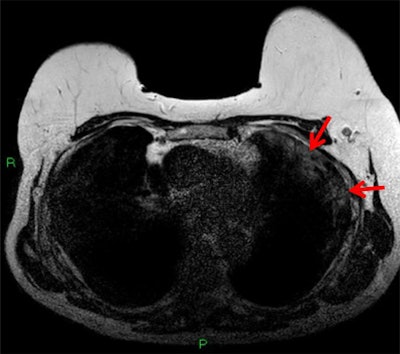

T1-weighted postcontrast fat-saturated MRI depicting subpleural consolidation enhancement (red arrows).The case also highlights the importance of looking for incidental findings on images that at least partially visualize the lungs. This not only includes breast MRI but also shoulder trauma imaging and some abdominal CT and MRI, the authors noted.